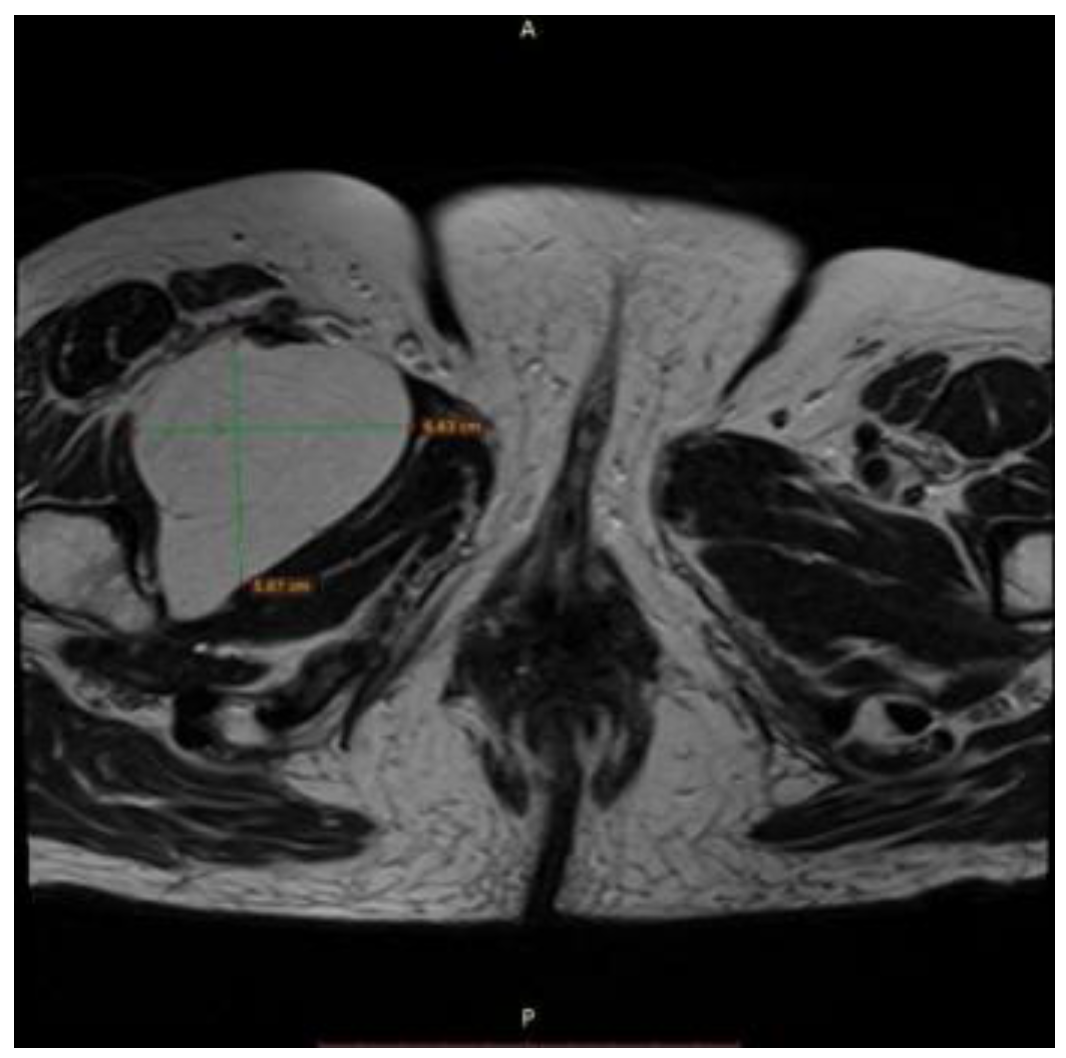

Asymptomatic Retroperitoneal Lipoma with Extension to the Right Anteromedial Thigh

2. Case Presentation